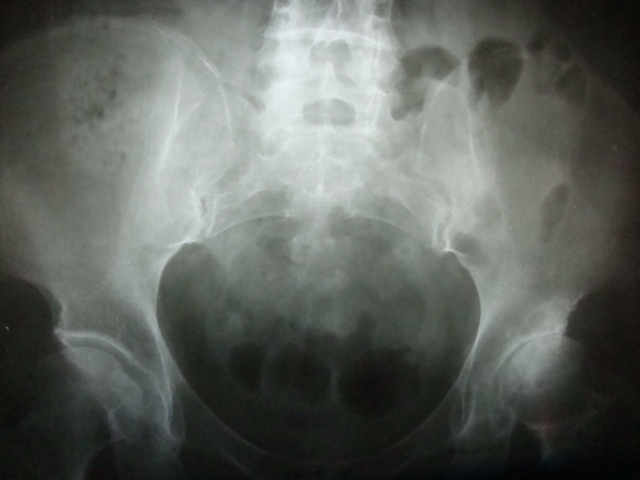

患者女58岁左腿跛行数月。

左侧髋关节间隙明显变窄,髋臼上缘硬化,左股骨头骨质未见明显异常,首先考虑左侧髋关节退变,可结合ct或mri检查看有否股骨头坏死。

成人髋臼发育不良 引起的退变

双侧髋臼发育不良继发退变,左侧无菌性坏死可疑。

左髋关节间隙明显变窄,髋臼上缘硬化。左股骨头可见斑点状密度减低区。双髋臼稍扁平。考虑双髋关节发育不良导致退变。建议mri排除左股骨头坏死

髋臼发育不良性骨关节病

左髋关节发育不良所致退行性变,股骨头缺血性坏死早期少有关节间隙的改变

左侧髋关节发育不良并退行性病变